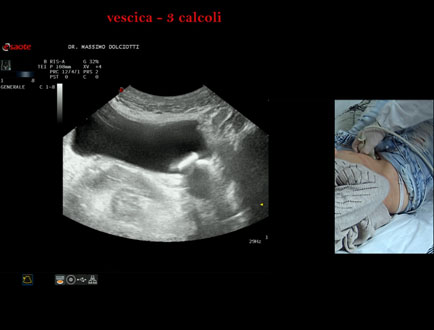

Data inserimento: 21/10/2025

Ecografia del: 15/10/2025

Strumento: Esaote MyLab Eight

Sonda: Convex Multifrequenza 1-8 MHz

Età Paziente: F 45 anni

Motivazione dell'esame: da alcuni mesi, disuria ed infezioni urinarie recidivanti.

Commento all'esame: le immagini ed il video documentano 3 immagini iperecogene, con cono d'ombra posteriore, da ricondurre a litiasi multipla della vescica.

Conclusioni: 3 calcoli della vescica (3 bladder stones).